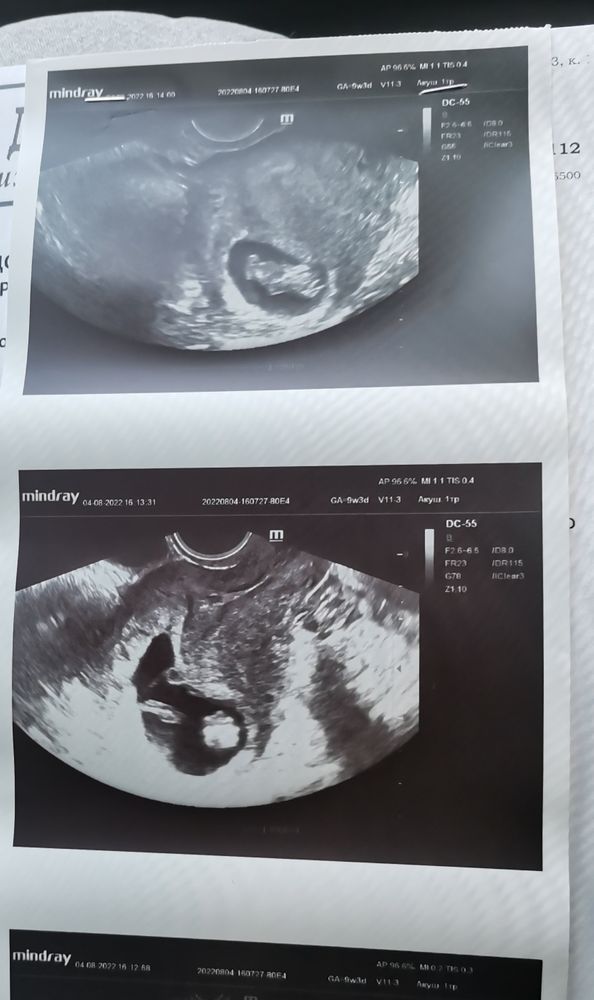

Есть ещё метод Рамзи, не смогла разобраться с ним, кто нибудь понимает?) С какой стороны расположен хорион? Слева или справа? У меня написано только по передней стенке и все 😁 Кто не занимается такой фигней прошу не писать 😁😁

Юлия *, ты видишь угол на снимке? Честно,мне там ничего не видно... 🤷♀️Но там ещё по прикреплению вроде можно посмотреть...

Даххха Мечтаю родить ДОЧКУ, какой угол? Смотрят по расположению хориона вокруг плодного яйца.

Даххха Мечтаю родить ДОЧКУ, Рамзи до 8 нед смотрят, дальше неинформативно.